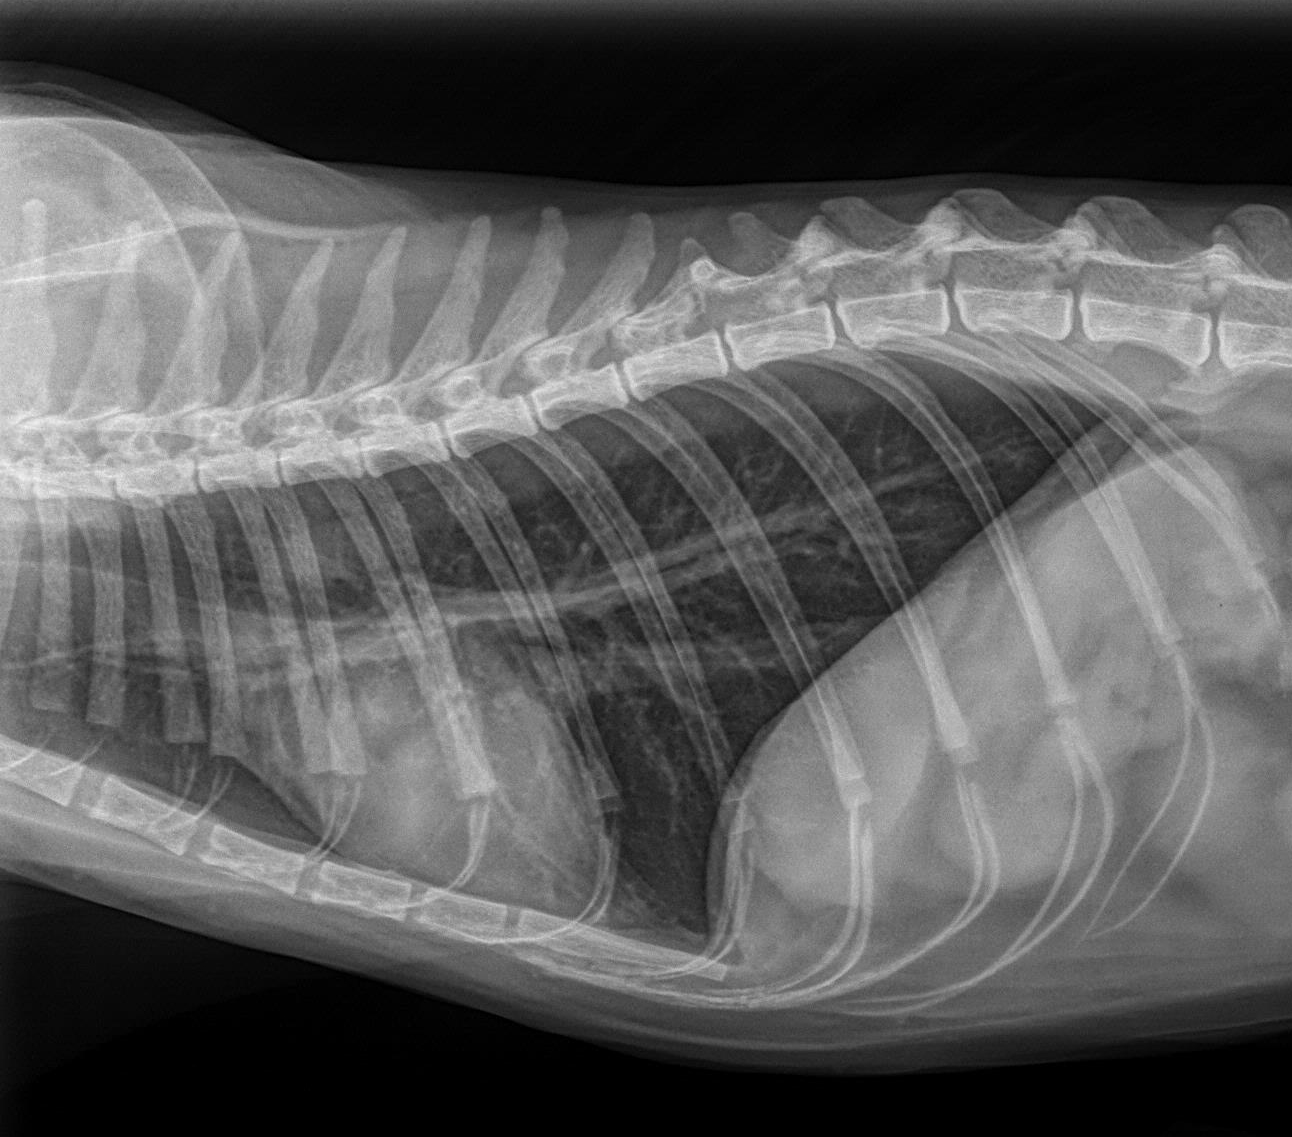

2犬猫胸腔积液和肺水肿的X光片诊断阅读 (1945)